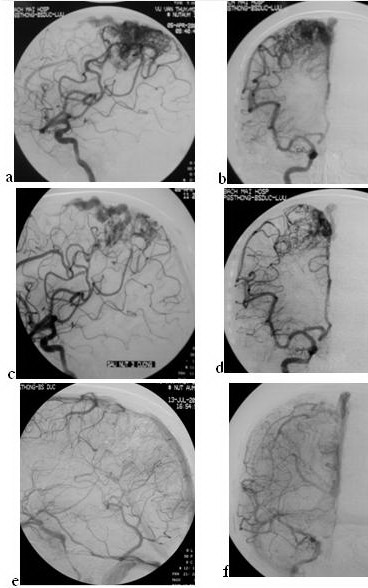

Trường hợp 3: tổn thương lớn, nhiều cuống, nút 3 lần 6 cuống.

Hình 3:

Bệnh nhân nam 37 tuổi, động kinh nhiều năm, khám phát chụp CLVT phát hiện DDĐTM

não; chụp mạch: ổ dị dạng vùng trán phải (vùng vận động) kích thước 3 x 5cm, có

nhiều cuống nuôi từ Đm não giữa và trước, tĩnh mạch dẫn lưu nông

(Spetzler-Martin III); Nút mạch lần I (01.02.07): gây tắc 2 cuống não giữa,

cuống 1 bơm 0.5ml với tỷ lệ Histoacry l/ Lipiodol: 0.5ml/2.0ml, cuống 2 bơm

0.25ml (0.5 ml/2.5 ml), gây tắc được khoảng 30% thể tích ổ dị dạng, sau nút không

còn thấy động kinh. Nút mạch lần II (05.04.07): trước nút (a,b) thấy ổ dị dạng

còn lớn, gây tắc 3 cuống não giữa với thể tích lần lượt là 0.9ml, 0.6ml và

1.4ml với cùng tỷ lệ (0.5ml/2.4ml), tắc được

khoảng 80% (c,d). Nút mạch lần III (13.07.07): gây tắc 1 cuống não trước bơm

0.5ml (0.5ml/2.4ml), chụp kiểm tra sau nút: tắc hoàn toàn ổ dị dạng (e,f). Sau

nút lần 3 đến nay (sau một tháng) không thấy động kinh.

Hình 3:

Bệnh nhân nam 37 tuổi, động kinh nhiều năm, khám phát chụp CLVT phát hiện DDĐTM

não; chụp mạch: ổ dị dạng vùng trán phải (vùng vận động) kích thước 3 x 5cm, có

nhiều cuống nuôi từ Đm não giữa và trước, tĩnh mạch dẫn lưu nông

(Spetzler-Martin III); Nút mạch lần I (01.02.07): gây tắc 2 cuống não giữa,

cuống 1 bơm 0.5ml với tỷ lệ Histoacry l/ Lipiodol: 0.5ml/2.0ml, cuống 2 bơm

0.25ml (0.5 ml/2.5 ml), gây tắc được khoảng 30% thể tích ổ dị dạng, sau nút không

còn thấy động kinh. Nút mạch lần II (05.04.07): trước nút (a,b) thấy ổ dị dạng

còn lớn, gây tắc 3 cuống não giữa với thể tích lần lượt là 0.9ml, 0.6ml và

1.4ml với cùng tỷ lệ (0.5ml/2.4ml), tắc được

khoảng 80% (c,d). Nút mạch lần III (13.07.07): gây tắc 1 cuống não trước bơm

0.5ml (0.5ml/2.4ml), chụp kiểm tra sau nút: tắc hoàn toàn ổ dị dạng (e,f). Sau

nút lần 3 đến nay (sau một tháng) không thấy động kinh.